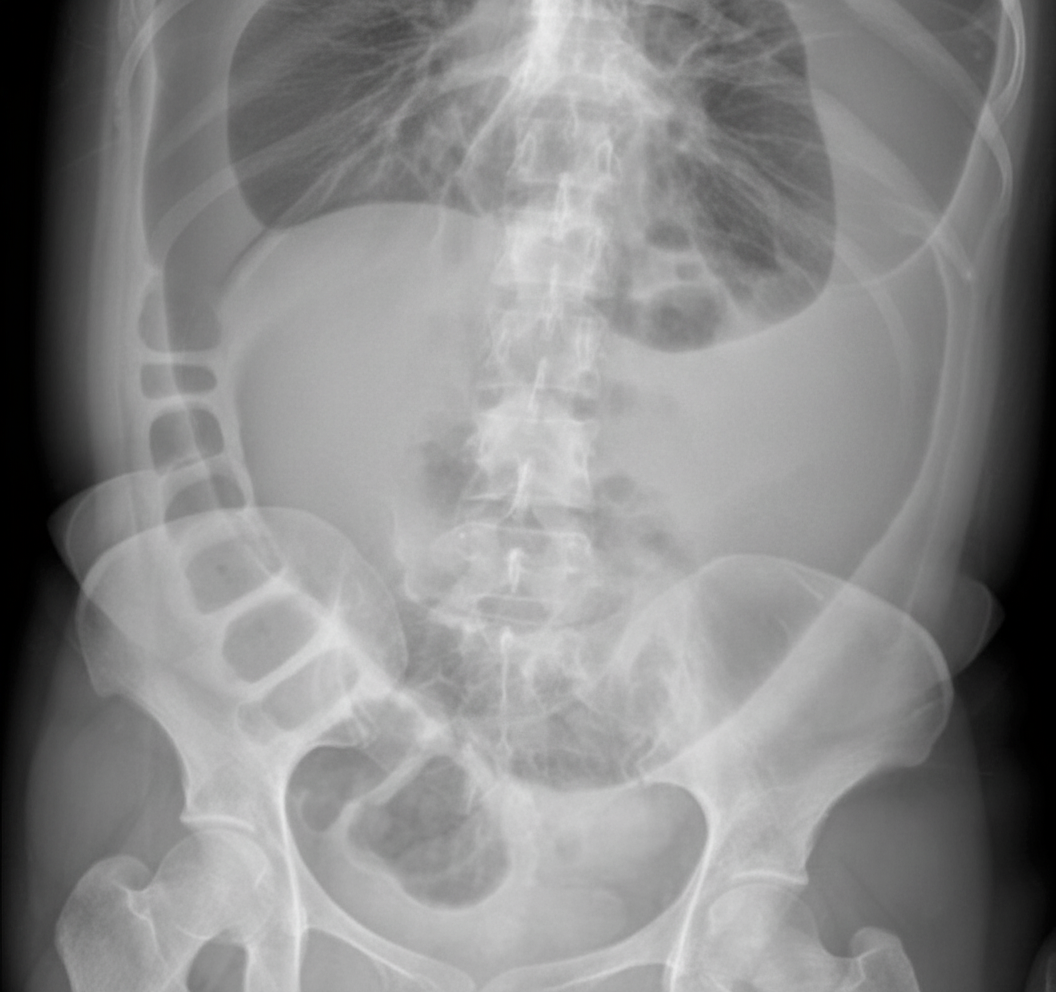

A 70-year-old male presents with colicky pain in the lower abdomen, with non-passage of feces and flatus. Abdominal X-ray findings are provided. Which of the following is the preferred treatment option for this patient?

Explanation: ***Colonoscopic detorsion followed by elective sigmoid colectomy*** - **Colonoscopic detorsion** provides immediate relief of the **sigmoid volvulus** obstruction, while **elective sigmoid colectomy** prevents recurrence, which occurs in up to **90%** of cases if only detorsion is performed. - This **two-stage approach** allows for patient stabilization and bowel preparation, reducing surgical mortality compared to emergency resection in an unprepared colon. *Colonoscopic detorsion* - While effective for immediate decompression of **sigmoid volvulus**, it has a very high **recurrence rate (90%)** if used as sole treatment. - Does not address the underlying **redundant sigmoid colon** and **elongated mesentery** that predispose to volvulus formation. *Elective sigmoid colectomy* - Cannot be performed as the initial treatment in this acute setting due to **bowel obstruction** and lack of adequate bowel preparation. - Emergency resection in an unprepared, distended colon carries significantly higher **morbidity and mortality** rates. *Paul-Mikulicz operation* - This is a **three-stage procedure** (exteriorization, resection, anastomosis) that is unnecessarily complex for sigmoid volvulus management. - Reserved for cases with **bowel perforation** or **gangrene**, which are not indicated in this stable presentation with viable bowel.